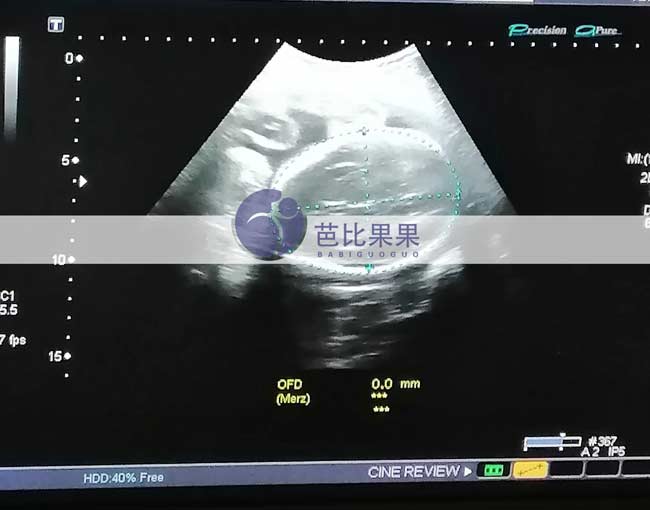

昆明Z女士家的乌克兰试管妈妈按时来医院28周的B超孕检

昆明Z女士家的乌克兰试管妈妈按时来医院做了28周的B超孕检,得知胎儿发育得很好,妈妈露出开心的笑容